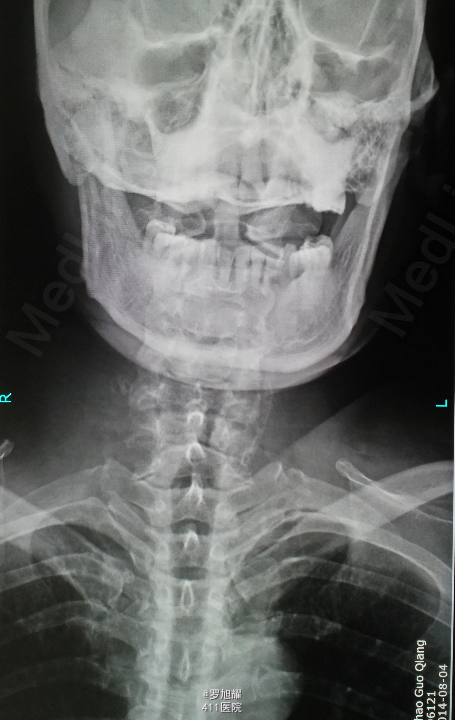

患者男性,64岁。因车祸致颈部疼痛、四肢麻木乏力2小时入院。 该患者同时还有头皮血肿、轻型闭合性颅脑损伤,后期再确诊右肩袖损伤。

左侧锁骨平面以下痛温觉、位置觉消失,右半身感觉正常。会阴部感觉存在。左侧肢体肌力正常,右侧上下肢肌力0级。右侧腱反射均消失。影像学检查示双侧枢椎椎弓骨折,MRI脂肪抑制成像颈1-2平面脊髓信号略高。